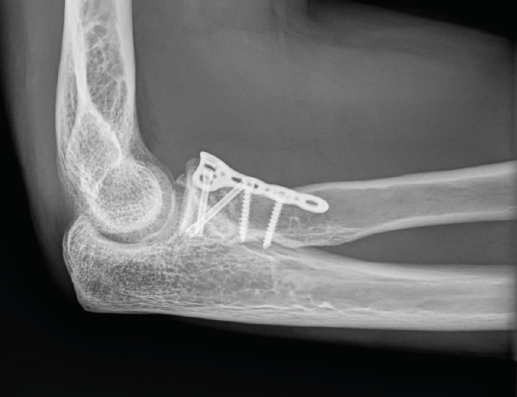

Fractura de Monteggia y lesiones Monteggia-like

Son lesiones poco frecuentes pero complejas. Es esencial una reconstrucción anatómica precisa del cúbito proximal para recuperar la funcionalidad del codo. La restauración anatómica de la longitud y las dimensiones del cúbito será crucial para la congruencia de la articulación radiocapitelar. Una reconstrucción fallida o inadecuada acabará con dolor persistente y una progresiva degeneración de la articulación. Hay que poner especial atención en 2 fragmentos: la faceta anteromedial de la coronoides y la faceta anterolateral del cúbito, junto a la cresta del supinador. La planificación preoperatoria es vital, por lo que recomendamos la TAC con reconstrucción 3D (Figura 9).

Figura 9. A: imagen en 3D de una fractura proximal compleja de cúbito y radio; B y C: radiografías de control tras la cirugía en otro caso de lesión Monteggia-like.

Precisarán siempre tratamiento quirúrgico. Usaremos un abordaje posterior extendido. En las fracturas de Monteggia, el radio recupera normalmente su congruencia una vez que hemos reducido la fractura del cúbito. En las lesiones complejas Monteggia-like, lo ideal es reducir primero el fragmento de coronoides al fragmento cubital distal, ya sea con AK temporales o añadiendo algún tornillo adicional. Es el contrafuerte anterior de la articulación y de más difícil acceso. Luego fijaremos el resto de los fragmentos a la diáfisis con una placa preconformada LCP(41,42,43). Trataremos la fractura de la cabeza del radio mediante osteosíntesis o preferiblemente con una prótesis. Por último, repararemos las lesiones ligamentosas con un anclaje si fuera necesario (Figura 9). Cuando la punta del olécranon es multifragmentaria, un solo tornillo no ofrece fijación suficiente, por lo que hay autores que proponen un cerclaje con sutura de alta resistencia desde el tendón del tríceps para reforzar la síntesis(44,45).